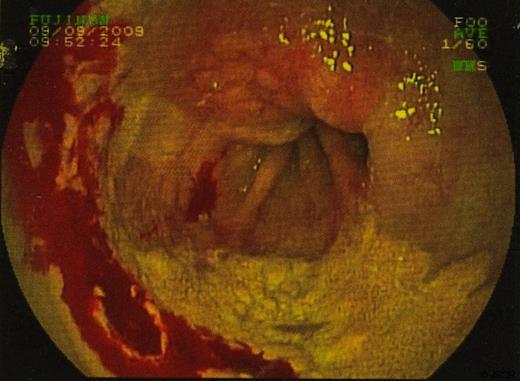

In September 2009 the patient underwent a colonoscopy and oesophagogastroduodenoscopy (OGD). Colonoscopy was unremarkable. However, views of the oesophagus on OGD showed what was thought to be a superficially spreading tumour, 35cm from the incisors and 5 cms in length. Barrett’s oesophagus was also seen. (figure 1 & 2)

Biopsies were taken and sent to histopathology. In some sections the cells viewed had small bland nuclei with foamy cytoplasm. They were negative for mucin stain and negative for epithelial markers. There was no dysplasia or malignancy. This picture was consistent with xanthalasma. Other biopsies of surrounding tissue showed a picture consistent with Barrett’s oesophagus. (Figure 3 & 4)